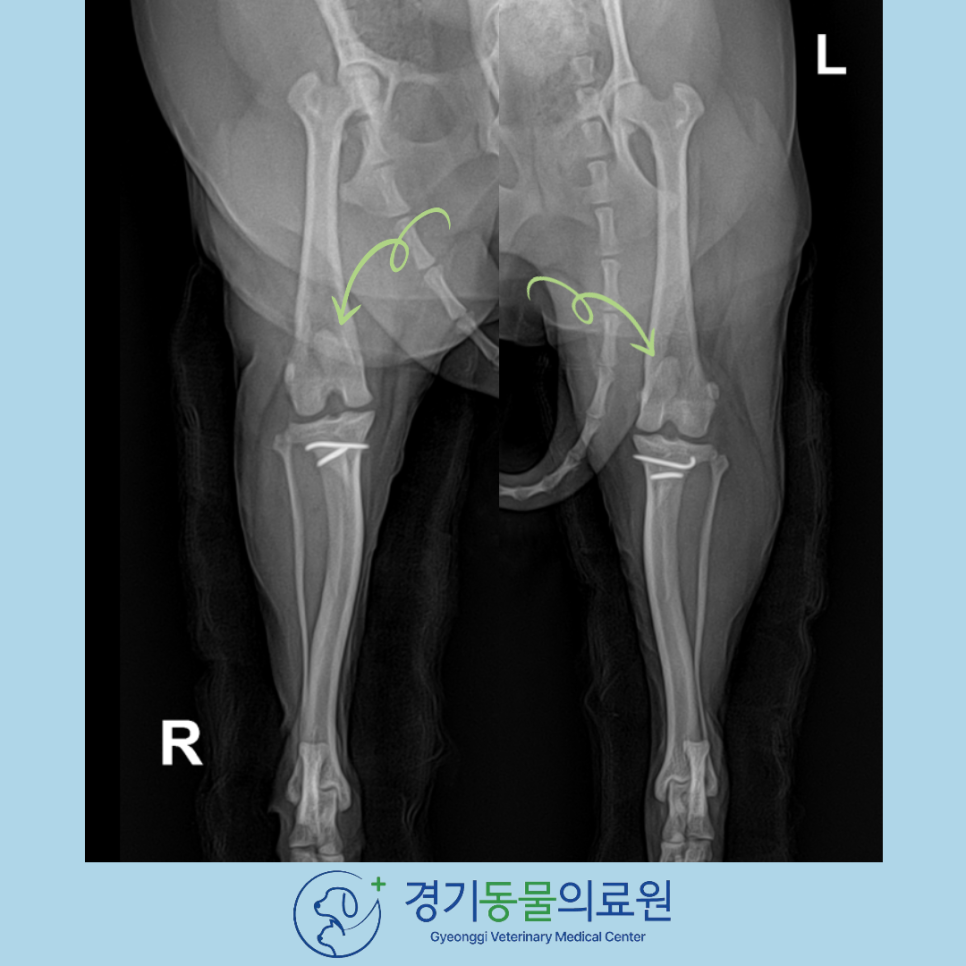

▶ 수술 후

수술 직후 X-ray 검사 화면입니다.

수술 전 내측으로 빠져있던 슬개골이 제 위치에 잘 환납것이 확인됩니다.